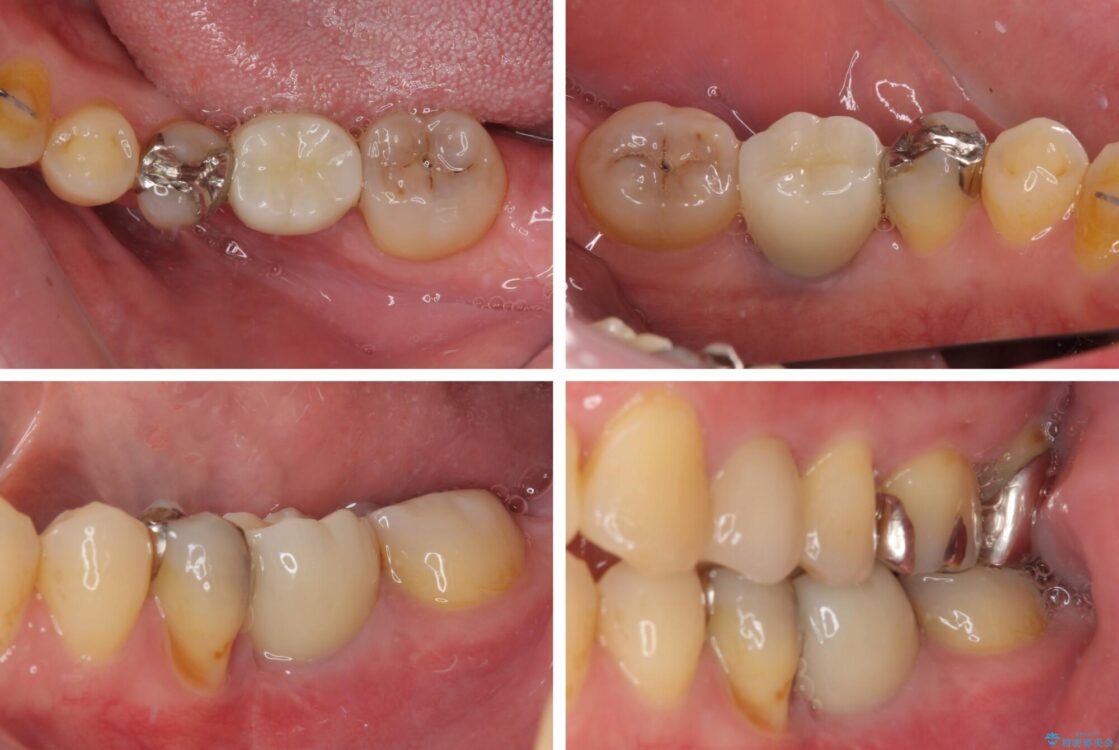

治療途中

• 割れてしまった奥歯とデコボコの前歯 矯正治療とインプラント治療 治療途中画像